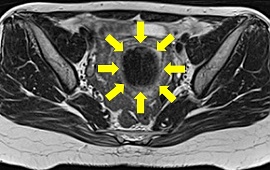

子宮筋腫に対する子宮動脈塞栓術(UAE)の実際

子宮動脈塞栓術(UAE)とは、子宮筋腫に栄養を与えている子宮動脈の血流を止めること

によって、筋腫を縮小させ、筋腫によって生じる過多月経などの症状を改善する治療法

です。足のつけ根に局所麻酔を行い、足のつけ根の動脈にカテーテルを入れ筋腫の近く

まで進めます。カテーテルから塞栓物質を注入し、血管を塞ぎ血流を止めます。塞栓が

完了したらカテーテルを抜き、傷口を押さえて止血します。

血管描出(塞栓前) 血管描出(塞栓後)

塞栓前MRI画像 塞栓後MRI画像